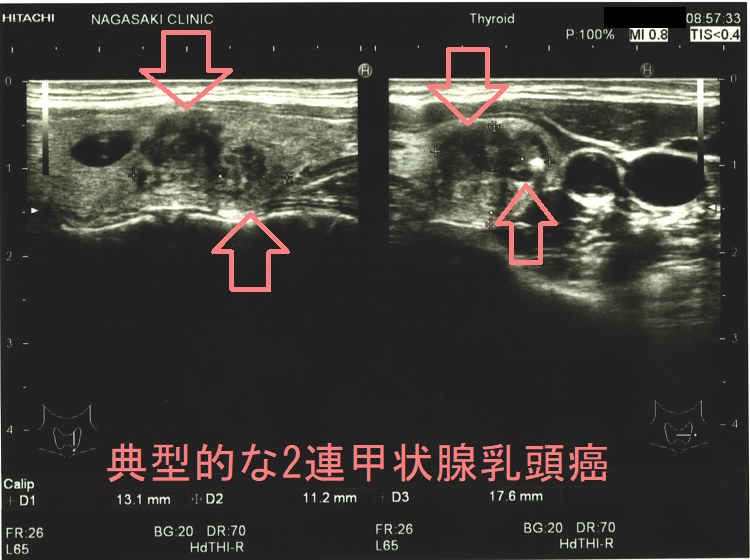

ケース⓪ 典型的な2連甲状腺乳頭癌

甲状腺乳頭癌の超音波エコー画像は境界不明瞭、不整形、粗雑、エコー輝度低く、砂粒状石灰化を伴う。エラストグラフィーで弾性硬~石様硬の硬さが多い。腺腫様結節と鑑別難でも細かい石灰化が異常に多い。解像度高い超音波エコー装置では微細石灰化の音響陰影が無く高エコースポットに見える。粗大石灰化を伴う甲状腺乳頭癌は細胞診で検体不適正率高いが、リンパ節転移・腺内多発・周囲組織浸潤が多い。腺腫様甲状腺腫内部に甲状腺乳頭癌組織が混じっている事も。甲状腺超音波エコー検査では明らかに甲状腺乳頭癌なのに、細胞診で確定診断できない場合もある。

甲状腺乳頭癌の超音波(エコー)画像は、境界不明瞭、不整形、粗雑、エコー輝度低く(黒く見える)、砂粒状石灰化と呼ばれる特徴的な石灰化があるのが典型的です。

増殖した甲状腺乳頭癌細胞はエコーを反射しないため極めて低エコー(黒く)に見える場合が多いです。(あまり黒くない場合もある)